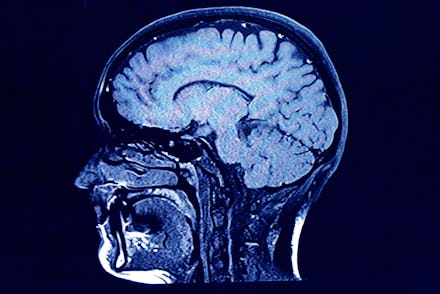

Scientists gathered 64 healthy men between the ages of 21 and 45 years and asked them questions about their pornography consumption. Then they imaged their brains.

"We found that the volume of the so-called striatum, a brain region that has been associated with reward processing and motivated behavior was smaller the more pornography consumption the participants reported," lead researcher Simone Kühn, who works with the Max Planck Institute for Human Development in Berlin, told Reuters.

"Moreover we found that another brain region, that is also part of the striatum that is active when people see sexual stimuli, shows less activation the more pornography participants consumed."